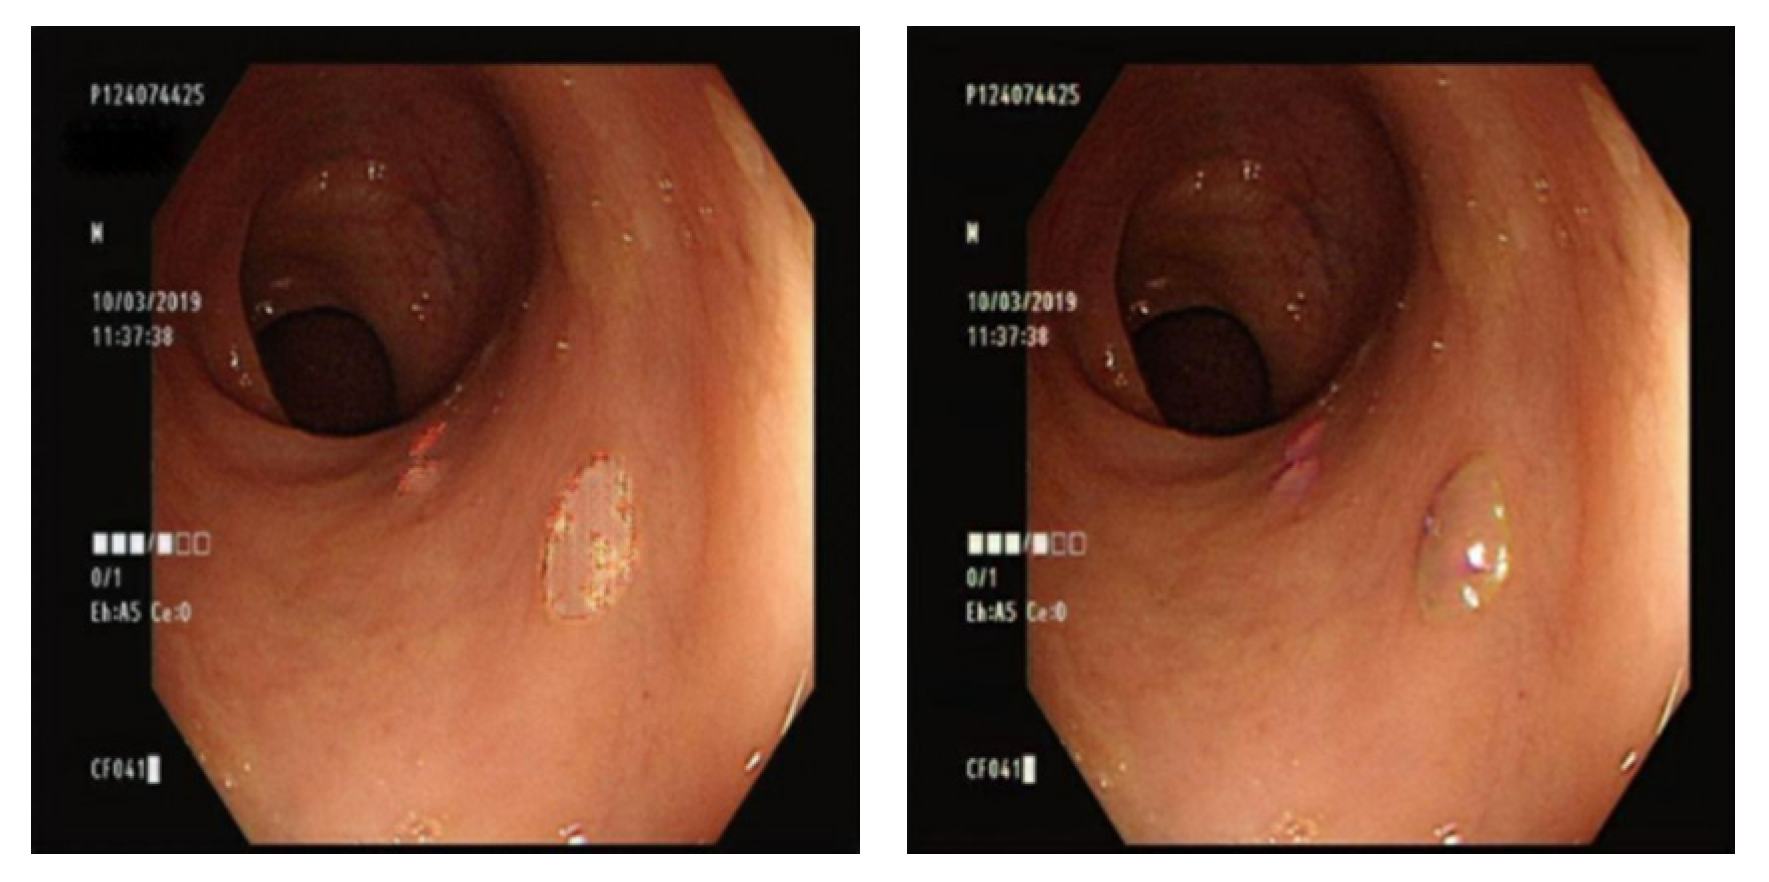

4.1. Comparison of GAN-Generated Images

3.7. Comparison of GAN Output

4.2. Comparison of YOLO Using Different Datasets